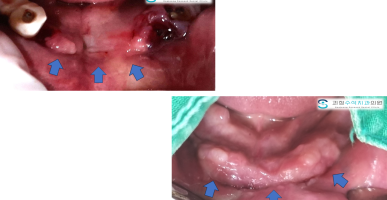

치조골 이식술 + 임플란트 식립

치조골(치아주변의 뼈)이 소실되어 발치후 치조골 이식술과 함께 임플란트를 식립한 사례입니다.